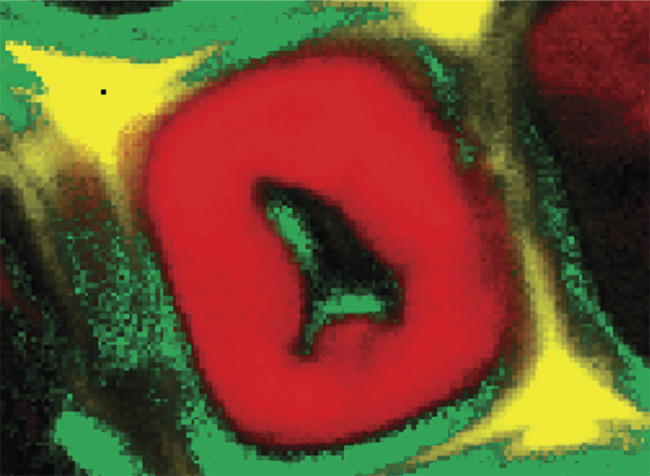

A Raman image of a poplar wood cell. Courtesy of WITec GmbH.